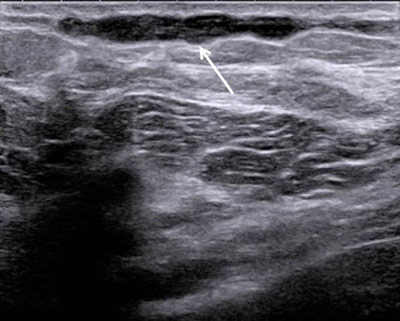

Figure 2

2D ultrasound: hypoechogenic subcutaneous and uncompressible linear structure.